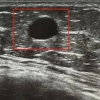

来自四川大学华西医院、绵阳市中心医院、川北医学院附属医院、四川省妇幼保健院、绵阳市第三人民医院、绵阳市404医院等知名医疗机构的26名专家学者,结合自己工作实际、研究课题、探索方向等主题,分别围绕鉬靶引导下真空辅助活检专题、超声引导下真空辅助乳腺活检临床实践指南、微创旋切术在特异性乳腺炎中的应用、HR +晚期乳腺癌内分泌治疗的联合时代、HR +年轻乳腺癌的争议与思考、病例分享等内容进行交流探讨;同时,通过面对面互动的形式,就参会嘉宾在实际诊疗工作中遇到的问题难点进行答疑释惑,进一步浓厚了开展乳腺微创的学术氛围、指明了发展乳腺学科的思路方向、强化了诊疗乳腺类疾病的信心能力。